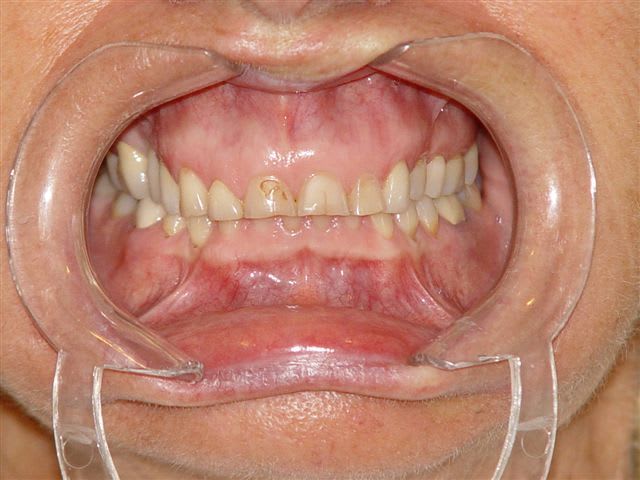

pour info et sans chirurgie, juste avec un machouilleur et le cerec

Perte de dvo laf6bw - Eugenol

Dvo à restaurer qjd6xd - Eugenol

Ainsi ntouaf - Eugenol

Cerec et e max xh3pat - Eugenol

Quand on voit l'usure des dents et la dvo actuelle, on peut tenter de réhausser les dents en désocclusion par des onlays comme je l'ai montré ci dessus, d'autant plus qu'à 78 ans le grand père de fluornet ne doit pas mourrir d'envie de repasser sur le billard avec un pronostic plus qu'alléatoire à mon humble avis, mais je pense que tout le monde a compris que je ne suis pas la diva du bistouri ce que je revendique haut et fort, les résultats de la dentosophie étant souvent bien plus satisfaisants que ceux des interventions chirurgicales maxillofaciales lourdes.